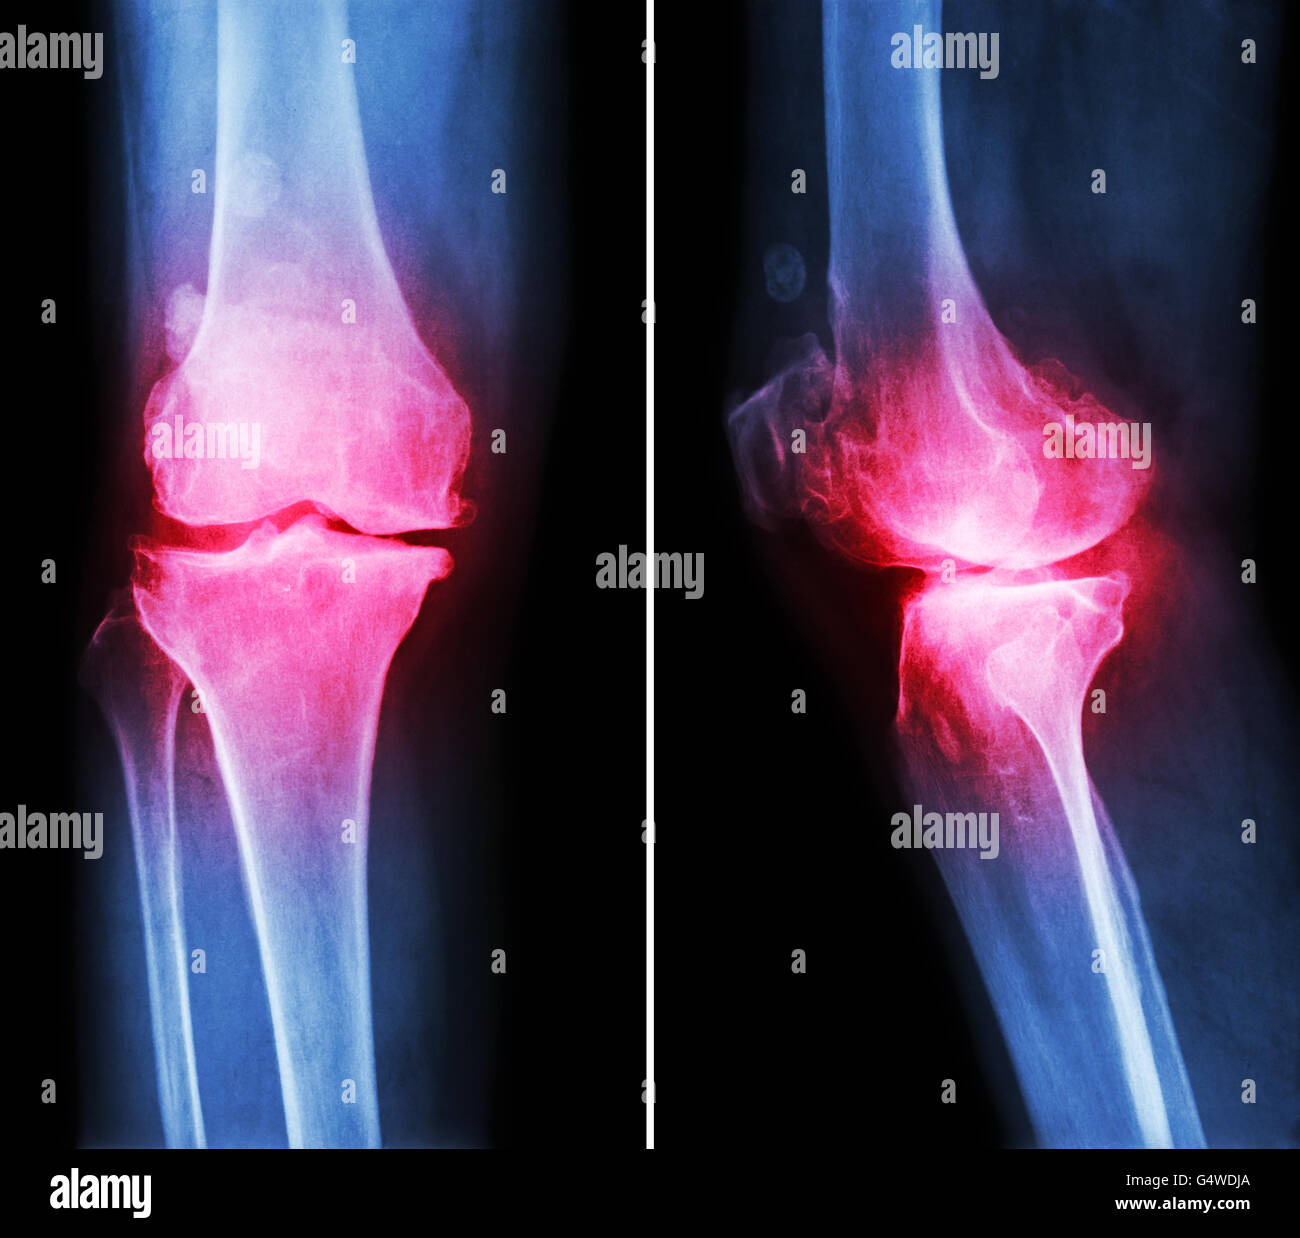

L'arthrose du genou . film x-ray ( genou - antérieure et postérieure vue latérale ) montre l'espace mixte étroit éperon ) , ('ostéophyte Banque D'Imageshttps://www.alamyimages.fr/image-license-details/?v=1https://www.alamyimages.fr/photo-image-l-arthrose-du-genou-film-x-ray-genou-anterieure-et-posterieure-vue-laterale-montre-l-espace-mixte-etroit-eperon-osteophyte-106280216.html

L'arthrose du genou . film x-ray ( genou - antérieure et postérieure vue latérale ) montre l'espace mixte étroit éperon ) , ('ostéophyte Banque D'Imageshttps://www.alamyimages.fr/image-license-details/?v=1https://www.alamyimages.fr/photo-image-l-arthrose-du-genou-film-x-ray-genou-anterieure-et-posterieure-vue-laterale-montre-l-espace-mixte-etroit-eperon-osteophyte-106280216.htmlRFG4WDE0–L'arthrose du genou . film x-ray ( genou - antérieure et postérieure vue latérale ) montre l'espace mixte étroit éperon ) , ('ostéophyte